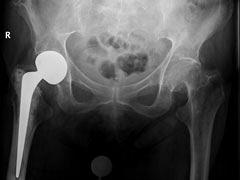

Met het toenemen van de leeftijd en fragiliteit wordt niet alleen de kans op vallen en dus op een heupfractuur groter, maar ook zijn de gevolgen daarvan ernstiger. In de preventie van vallen bij ouderen kan de fysiotherapeut een belangrijke taak vervullen. Naast specifieke training voor verhoging van spierkracht en mobiliteit kan de fysiotherapeut een rol hebben in het signaleren en corrigeren van factoren die het vallen kunnen bevorderen. Nadat een heupfractuur behandeld is in het ziekenhuis, vindt de revalidatie meestal thuis of in een revalidatiesetting plaats. Kennis van de verschillende behandelingen en complicaties bij collum femorisfracturen en pertrochantaire fracturen is van belang voor de fysiotherapeut. In de revalidatiefase is de fysiotherapeut vaak de spil van de zorg. Na het eerste herstel, het optimaliseren van de patiënt en verbeteren van medische, risico- en omgevingsfactoren is oefentherapie gericht op spierkrachtverbetering en balansherstel belangrijk voor een optimaal resultaat na een heupfractuur.

• kent u de verschillende typen heupfracturen

• heeft u kennis van de operatieve behandelopties van heupfracturen